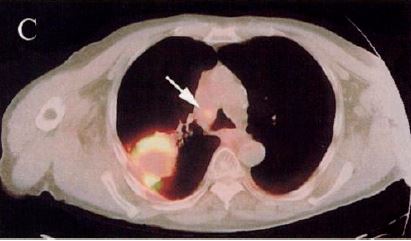

図10. PET-CT(2000年).肺癌とその縦隔転移(→)[40].

核医学画像の欠点のひとつに,解剖学的な局在情報の取得が難しいことが挙げられる.早くも1966年に,Kuhlらはtranmission scanと emission scanを同時に撮影する方法を提唱しているが,実用にはいたらなかった[36].この問題を根本的に解決したのが Geneva大学のDavid Townsend,Tennessee大学のRonald Nuttが1990年代に開発した,PETとCTを1台の装置に組込んで患者を移動することなく連続して撮影,画像を合成するPET-CTであった[37](図10).1998年にPittsburgh大学でプロトタイプが稼働し,特にFDGによる腫瘍診断における有用性が高く評価され,2001年にGE社(Discovery LS),次いでSiemens社(Biograph)により製品化された*.PET-CTは以後急速に普及し,2006年には単独PET装置は姿を消した[35].